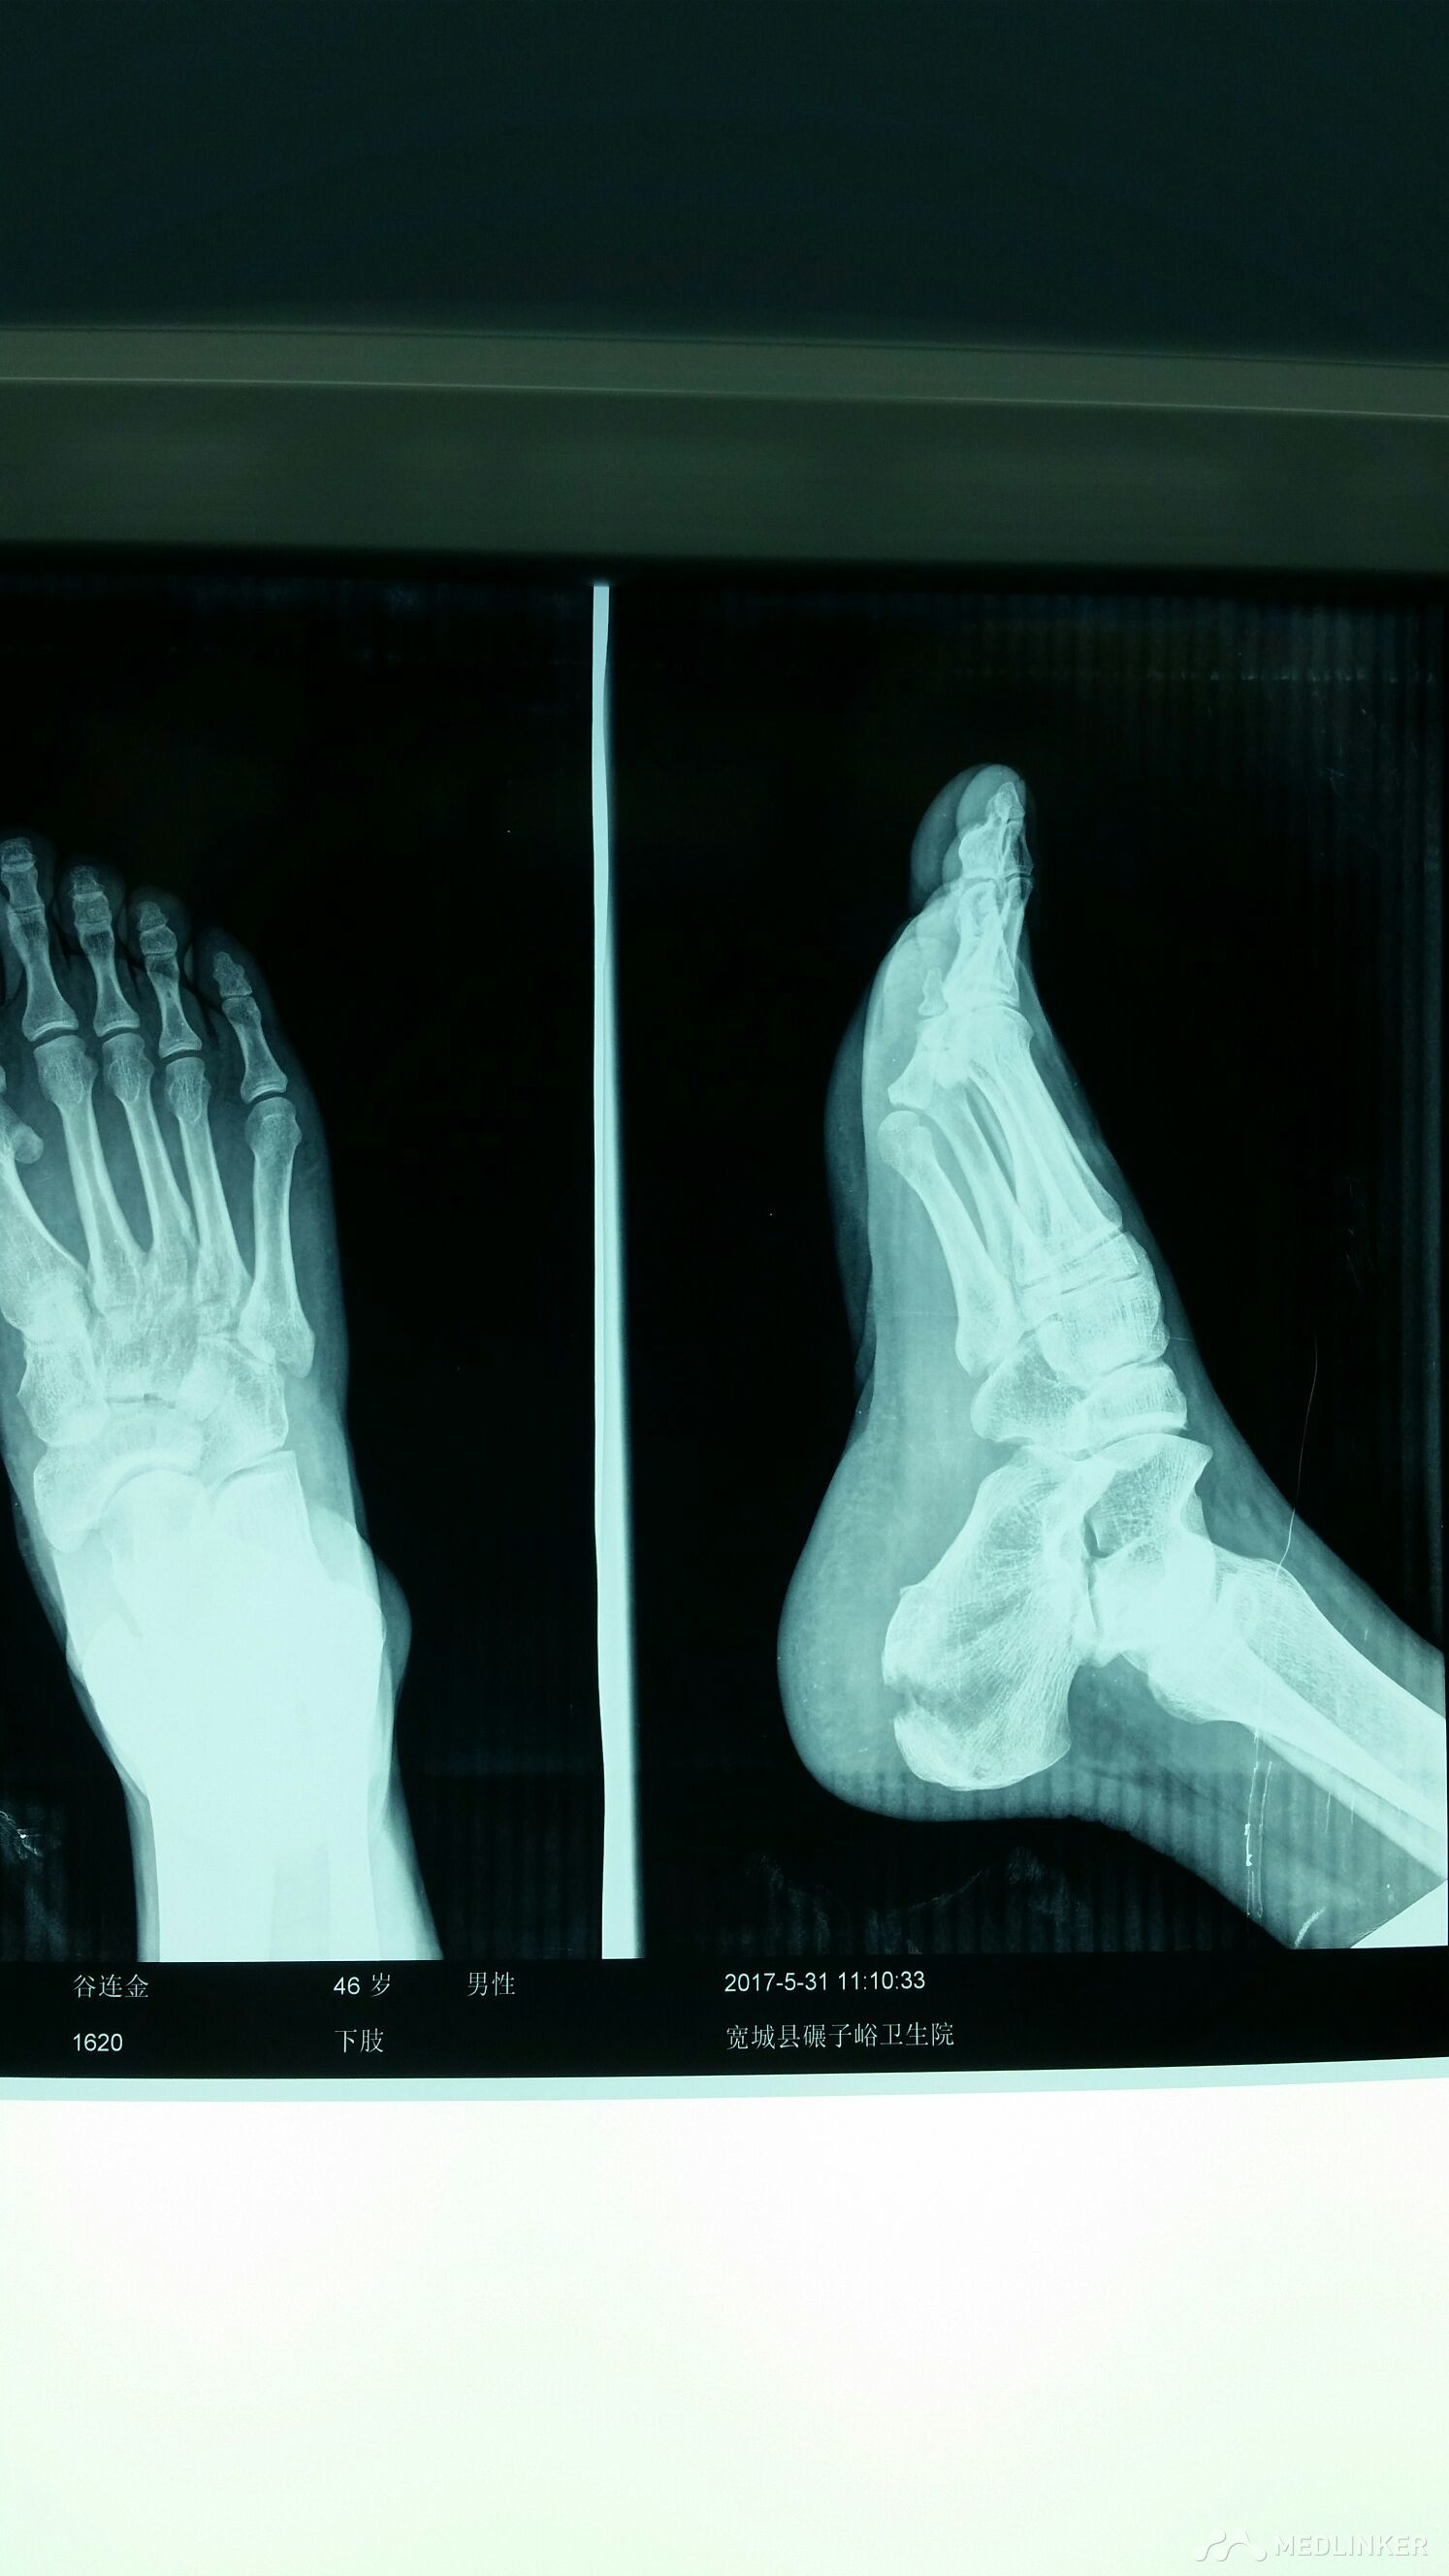

跟骨骨折

高处坠落致使右跟骨骨折